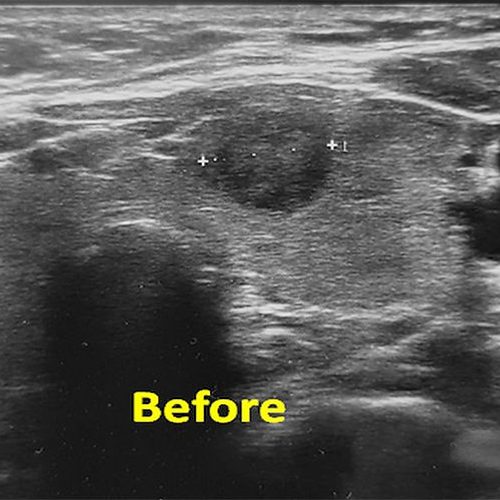

A 31 year old male with a 10cm benign solid nodule in the left thyroid lobe underwent embolization. Six months later, the volume of the nodule decreased by 90% and the appearance of the neck was practically normal.